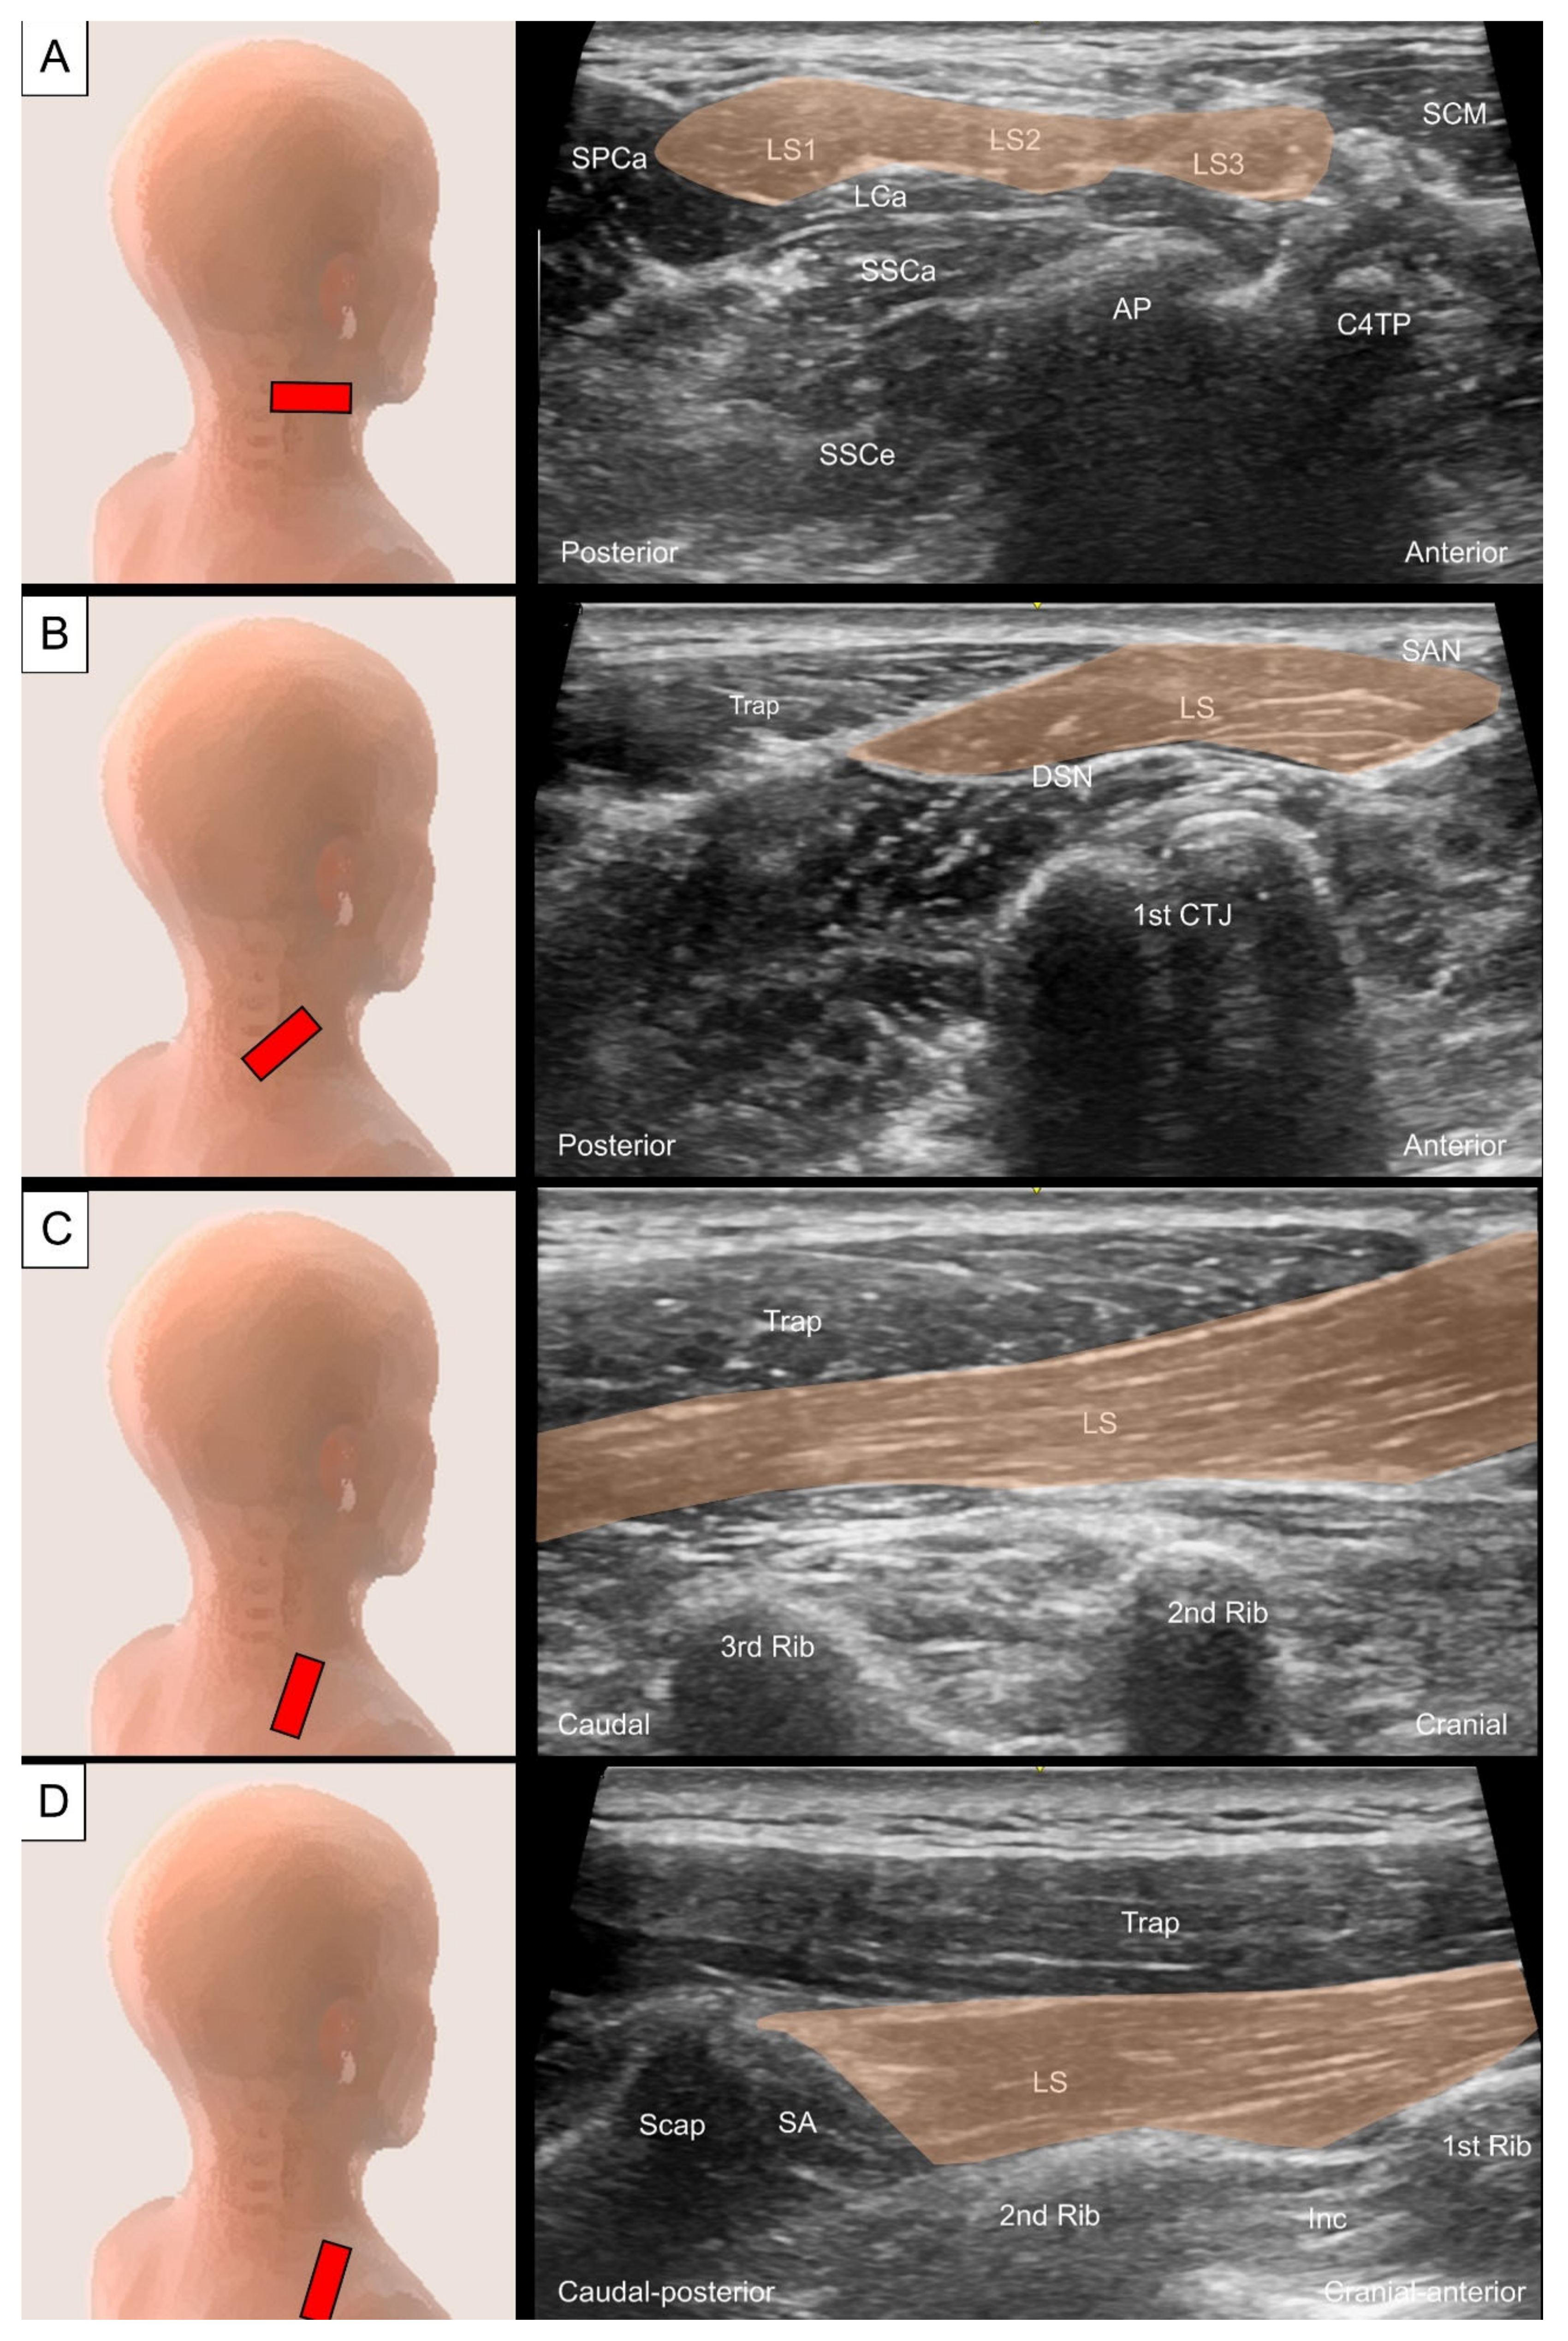

2.3. Levator Scapulae

2.3.1. Anatomy

2.3.2. Sonographic Scanning

2.3.3. Clinical Relevance